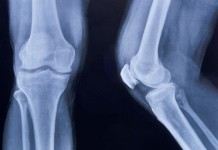

7 ранних признаков артрита

Причины болезней суставов могут быть одинаковыми, но их симптомы похожи не всегда. В этом слайд-шоу – о некоторых ранних признаках артрита и артроза.